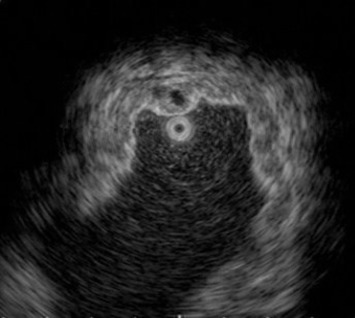

A barium upper gastrointestinal series radiography showed a suspected gastric tumor in the upper body with poor peristalsis and thickened mucosa (Fig. 2 A). An abdominal CT scan also revealed marked folds thickening in the gastric body without any obvious subserosal involvement. The impression from the radiologist was gastric cancer (Fig. 2 B). An EUS demonstrated circumferential thickening (up to 14.1 mm) of the second and third layers of the gastric wall with some anechoic cystic lesions (Fig. 3 ).

Endoscopic ultrasonography imaging. Circumferential thickening of second and ...

Figure 3.

Endoscopic ultrasonography imaging. Circumferential thickening of second and third layers of gastric wall with some anechoic cystic lesions.